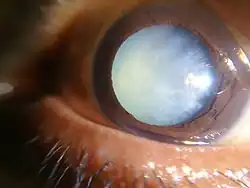

Posterior subcapsular cataract of a 16-year-old girl with type 1 diabetes

Posterior subcapsular cataract of a 16-year-old girl with type 1 diabetes -

Dense white mature cataract of a 60-year-old male

Dense white mature cataract of a 60-year-old male -